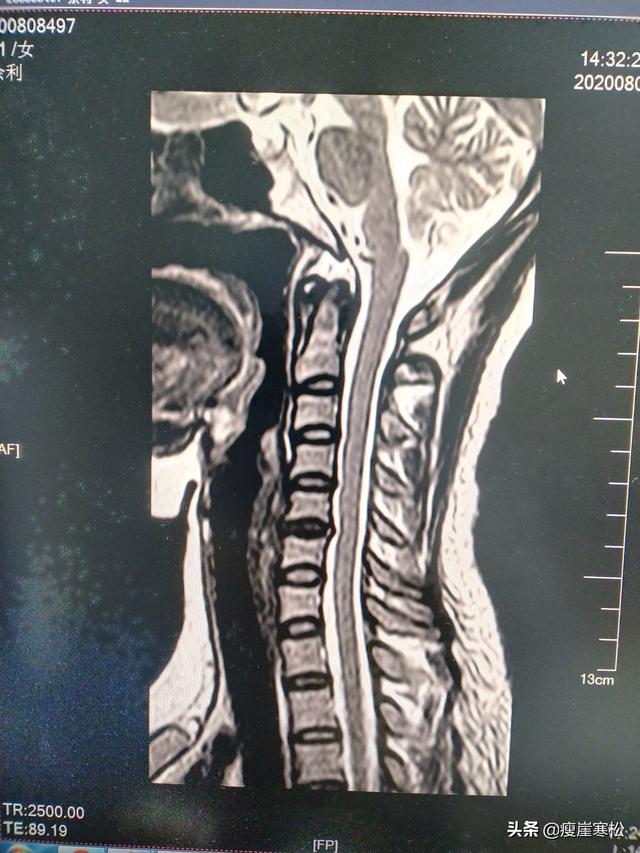

6. En cas de spondylose cervicale précoce, de douleurs au cou et aux épaules, de tension de la colonne cervicale, de redressement de la courbure physiologique et d'absence d'autres anomalies, l'IRM du disque révèle un risque d'accident vasculaire cérébral.

4, lorsque votre spondylose cervicale jusqu'à l'extrémité du disque dégénère gravement. Hernie ou même prolapsus, et semble comprimer le sac dural ainsi que la racine nerveuse des symptômes graves, les mains continuent à s'engourdir, des étourdissements, etc., ce qui suggère que vous, votre cerveau peut être l'approvisionnement en sang est gravement insuffisante, l'accident vasculaire cérébral apparaîtra dans votre côté non loin de là.

La spondylose cervicale est une cause fréquente d'infarctus cérébral. La colonne cervicale occupe une position particulière et constitue le passage obligé pour l'apport sanguin du cœur au cerveau. Une maladie de la colonne cervicale entraîne un spasme et une contraction des artères carotides et des vaisseaux sanguins de la région crânienne, ce qui affecte la circulation normale du sang et provoque un infarctus cérébral.